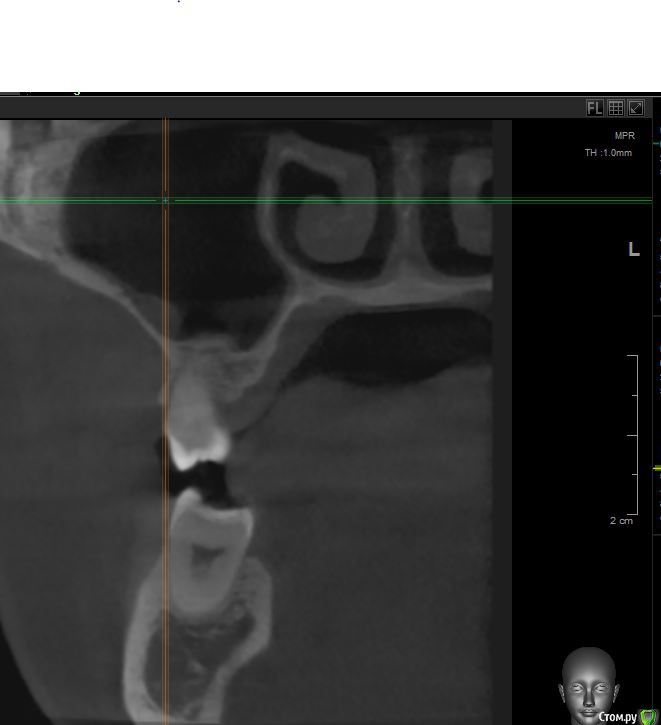

jm3300 Опубликовано 12 июля, 2016 Автор Поделиться Опубликовано 12 июля, 2016 А до операции КТ могли бы выложить? И сколько времени отсутствовали зубы в этой области?отсутствовали достаточно долги. КТ до: Ссылка на комментарий

jm3300 Опубликовано 14 июля, 2016 Автор Поделиться Опубликовано 14 июля, 2016 выкладываю кт Ссылка на комментарий

умножающий печаль Опубликовано 14 июля, 2016 Поделиться Опубликовано 14 июля, 2016 Промыть пазуху через соустье, курсом. Я отправляю к ЛОРам. Антибиотикотерапия, гипосенсибилизация. Один из винтов вестибулярно без костной поддержки, на мой взгляд. 1 Ссылка на комментарий

jm3300 Опубликовано 14 июля, 2016 Автор Поделиться Опубликовано 14 июля, 2016 Промыть пазуху через соустье, курсом. Я отправляю к ЛОРам. Антибиотикотерапия, гипосенсибилизация. Один из винтов вестибулярно без костной поддержки, на мой взгляд. гайморит всё таки есть? 1 Ссылка на комментарий

red_butler Опубликовано 15 июля, 2016 Поделиться Опубликовано 15 июля, 2016 гайморит всё таки есть?Не увидел, один винт похоже на выход 1 Ссылка на комментарий

syrovovec Опубликовано 15 июля, 2016 Поделиться Опубликовано 15 июля, 2016 (изменено) Пазуха чистая, Антон, какой винт на выход не понял?Может у пац аллергия ? Изменено 15 июля, 2016 пользователем syrovovec 1 Ссылка на комментарий

kladoffka Опубликовано 15 июля, 2016 Поделиться Опубликовано 15 июля, 2016 Тоже не понял, вроде все хорошо стоят. Главное слизистые то в покое. 1 Ссылка на комментарий

red_butler Опубликовано 15 июля, 2016 Поделиться Опубликовано 15 июля, 2016 Пазуха чистая, Антон, какой винт на выход не понял?Может у пац аллергия ?На последних срезах, вестибулярно на 2/3 кости нет.Какая уж аллергия, если боль и отек 1 Ссылка на комментарий

умножающий печаль Опубликовано 15 июля, 2016 Поделиться Опубликовано 15 июля, 2016 (изменено) гайморит всё таки есть?Судя по симптоматике, которую вы представили, есть. На снимке признаки могут запаздывать, ежели процесс острый, хотя снижение пневматизации должно быть заметно. Я на мониторе не разглядел. Рентген всего лишь доп. метод обследования. Диагноз ставит врач, то есть вы, сопоставив клинику и доп.методы.З.Ы. Я не думаю, что в вашем случае причина гайморита имплантация. Временной интервал слишком велик. Изменено 15 июля, 2016 пользователем умножающий печаль 1 Ссылка на комментарий

умножающий печаль Опубликовано 15 июля, 2016 Поделиться Опубликовано 15 июля, 2016 Тоже не понял, вроде все хорошо стоят. Главное слизистые то в покое.Это пока в покое. Винт не покрытый костью, долго под мягкими тканями оставаться не будет. Неизбежна рецессия со всеми вытекающими. 1 Ссылка на комментарий